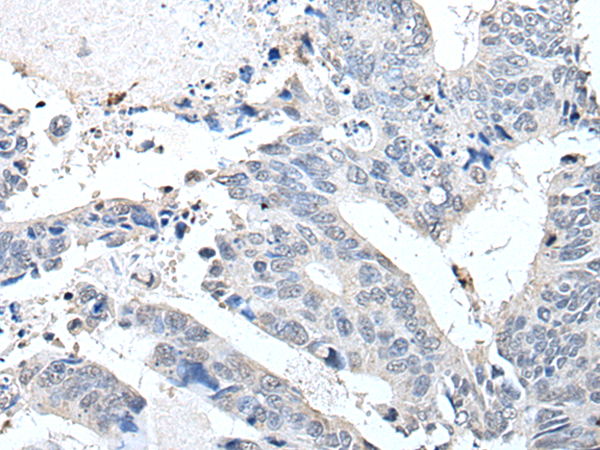

分类: 科研抗体货号: P08654别名: IA2; IA-2; ICA512; R-PTP-N; IA-2/PTP应用: IHC反应种属: Human, Mouse, Rat